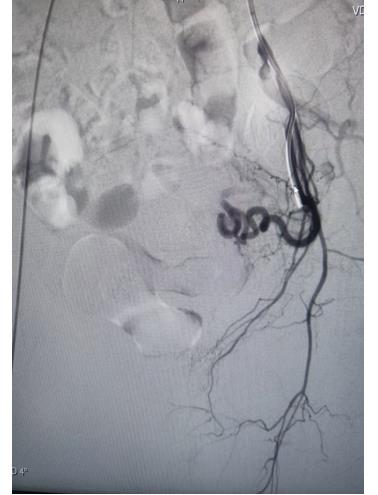

冠脉手术前

但患者还有子宫肌瘤长年不规则出血,支架术后需要抗凝、抗血小板聚集治疗,这样加重了子宫异常出血;半年前患者因长期子宫出血不止导致重度贫血进行输血治疗,为此患者痛苦不堪;经过详细检查患者合并有子宫肌瘤,经过崔旭辉主任认真研判,考虑绝经期女性,该患者目前最佳选择是行子宫动脉栓塞术。

子宫动脉栓塞术属于血管介入性治疗,方法是于股动脉穿刺进针插入导管,在X射线造影下定位进入两侧子宫动脉,注入栓塞剂完全栓塞子宫动脉,从而达到止血或让子宫肌瘤和病灶缺血坏死的目的;2022年12月6日,在崔旭辉主任、孟庆槐副主任医师、马力主治医师等我院介入团队协作下,成功为患者进行了双侧子宫动脉栓塞术,术后患者子宫异常出血停止,效果立竿见影,患者病情恢复良好。